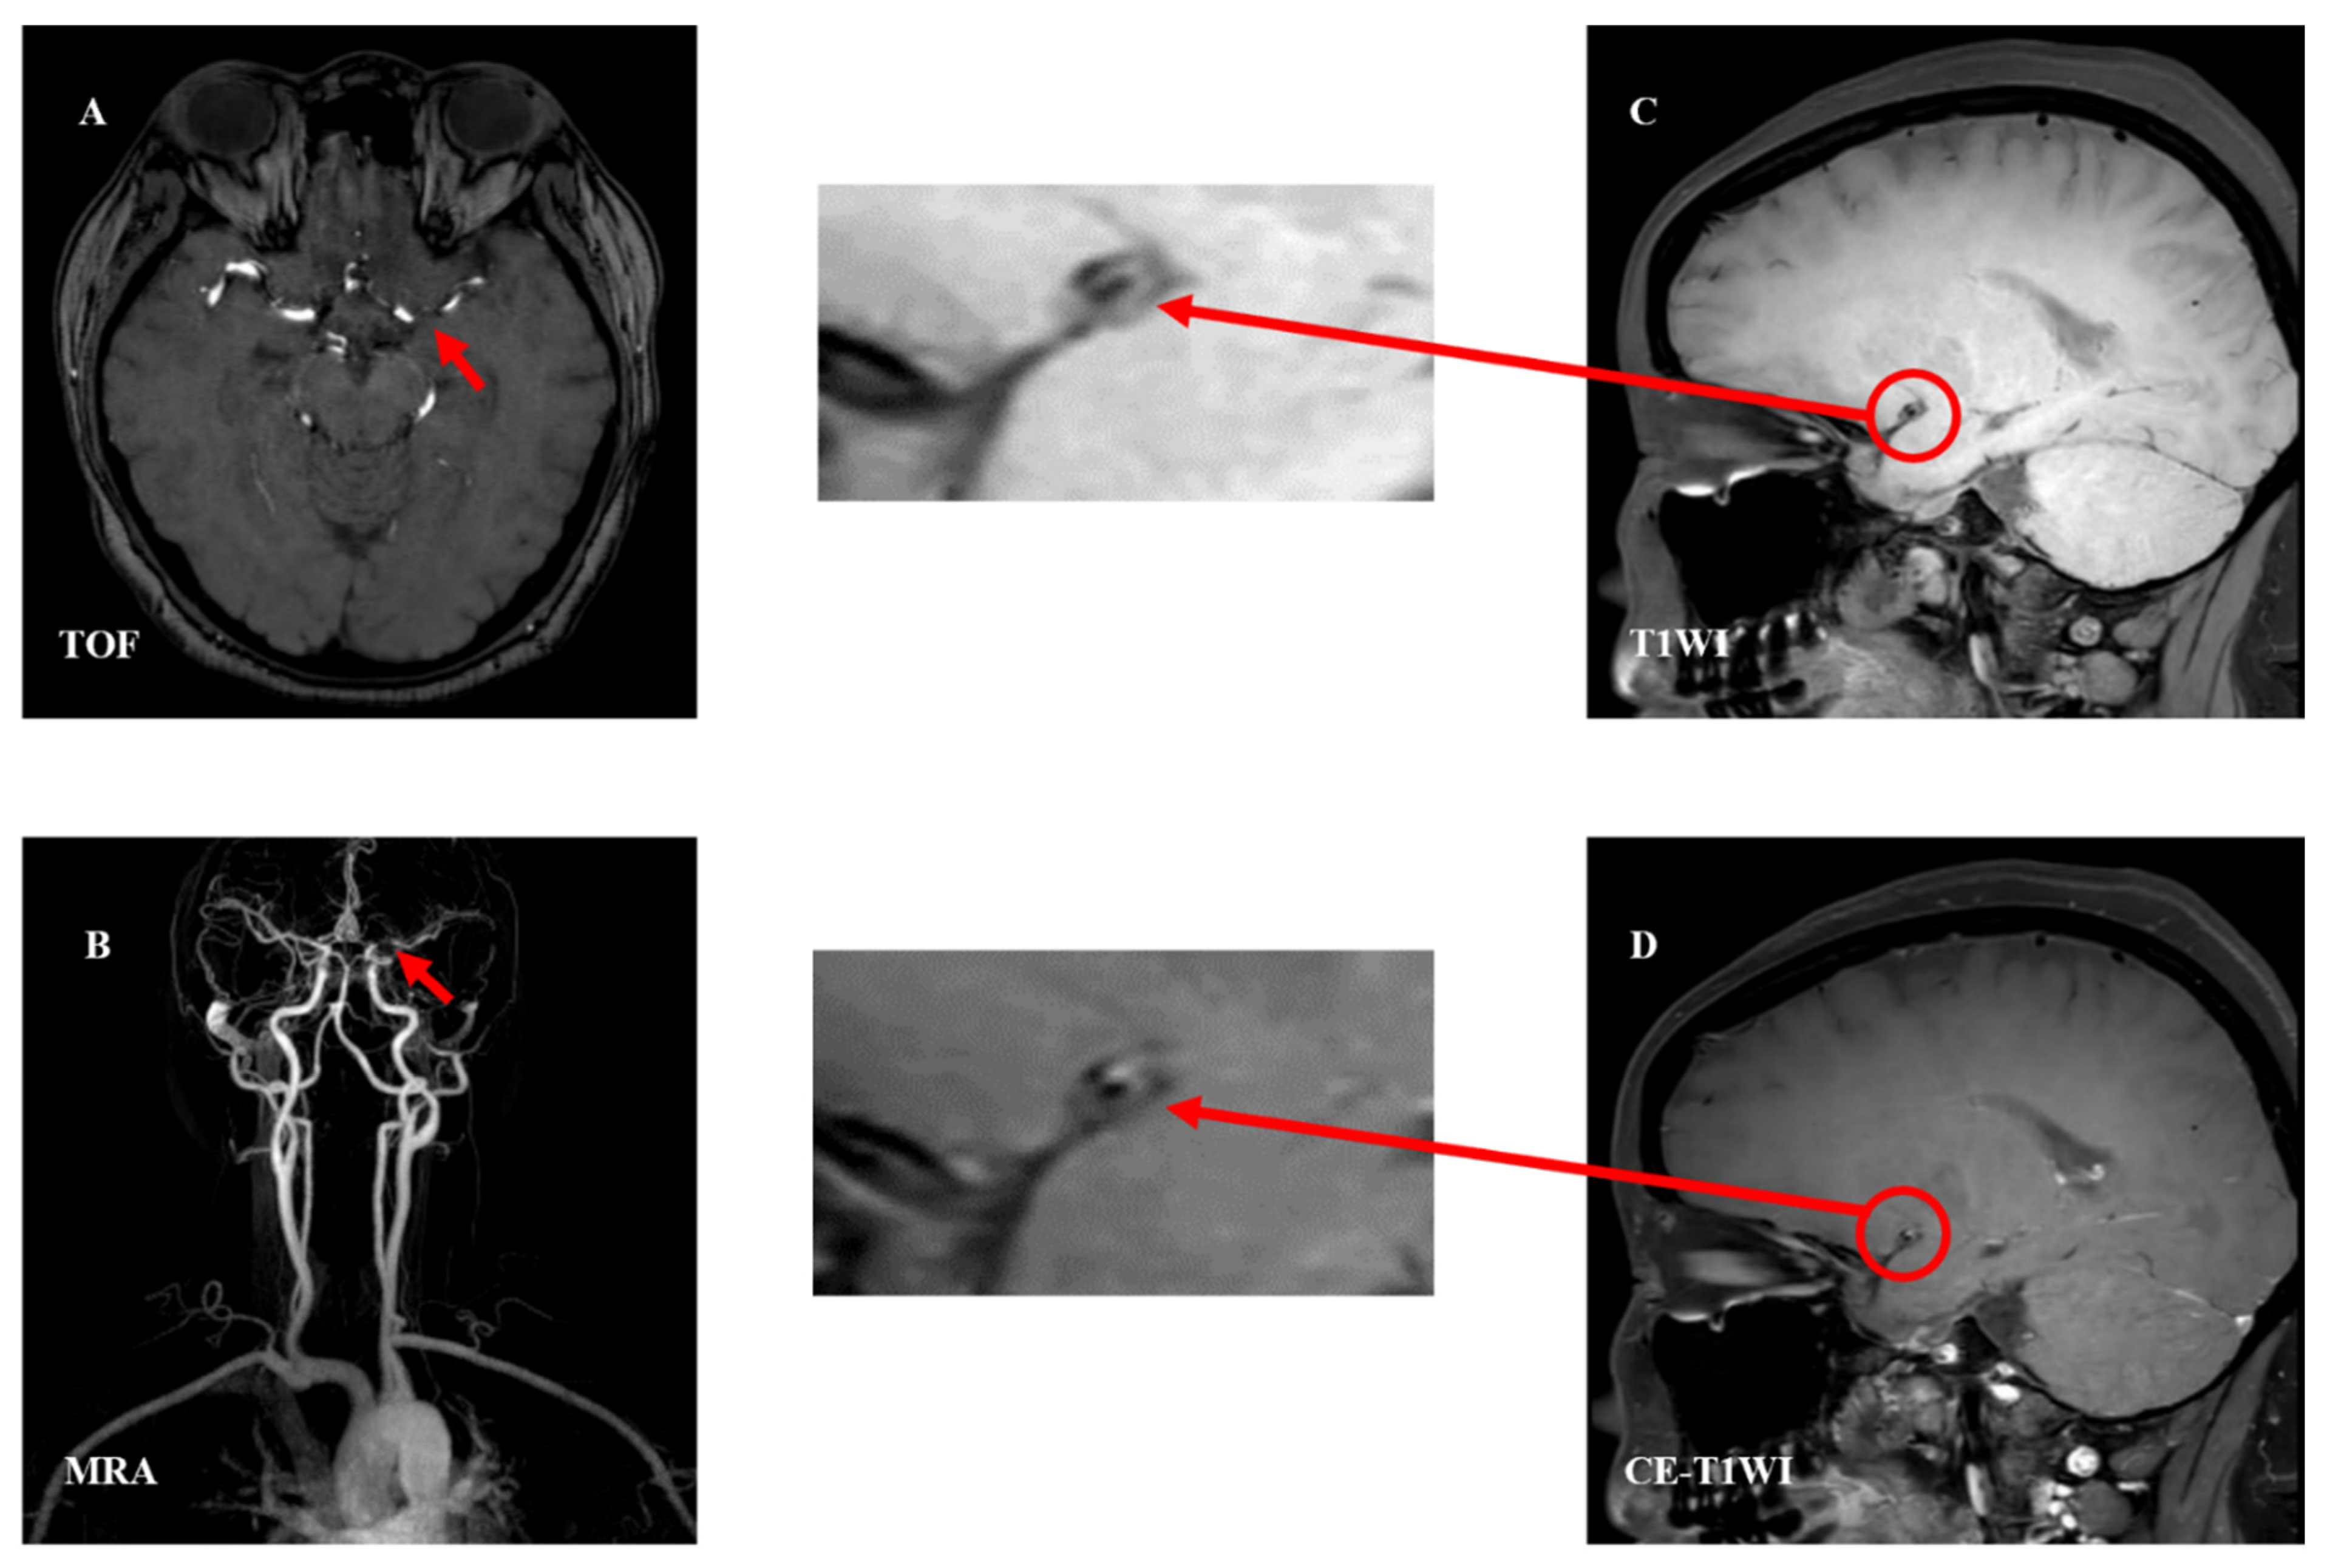

| Plaque Components | TOF | T1WI | T2WI | PDWI | CE-T1WI |

|---|---|---|---|---|---|

| Lipid cores | isointensity | isointensity/ hyperintensity | hypointensity | isointensity/ hyperintensity | - |

| Fibrous caps | isointensity | isointensity/ hyperintensity | isointensity/ hyperintensity | isointensity/ hyperintensity | + |

| Intraplaque hemorrhage | |||||

| Fresh (<1 w) | hyperintensity | hyperintensity | isointensity/ hypointensity | isointensity/ hypointensity | - |

| Recent (1–6 w) | hyperintensity | hyperintensity | hyperintensity | hyperintensity | - |

| Chronic (>6 w) | hypointensity | hypointensity | hypointensity | hypointensity | - |

| Calcification | Heavy hypointensity | Heavy hypointensity | Heavy hypointensity | Heavy hypointensity | - |